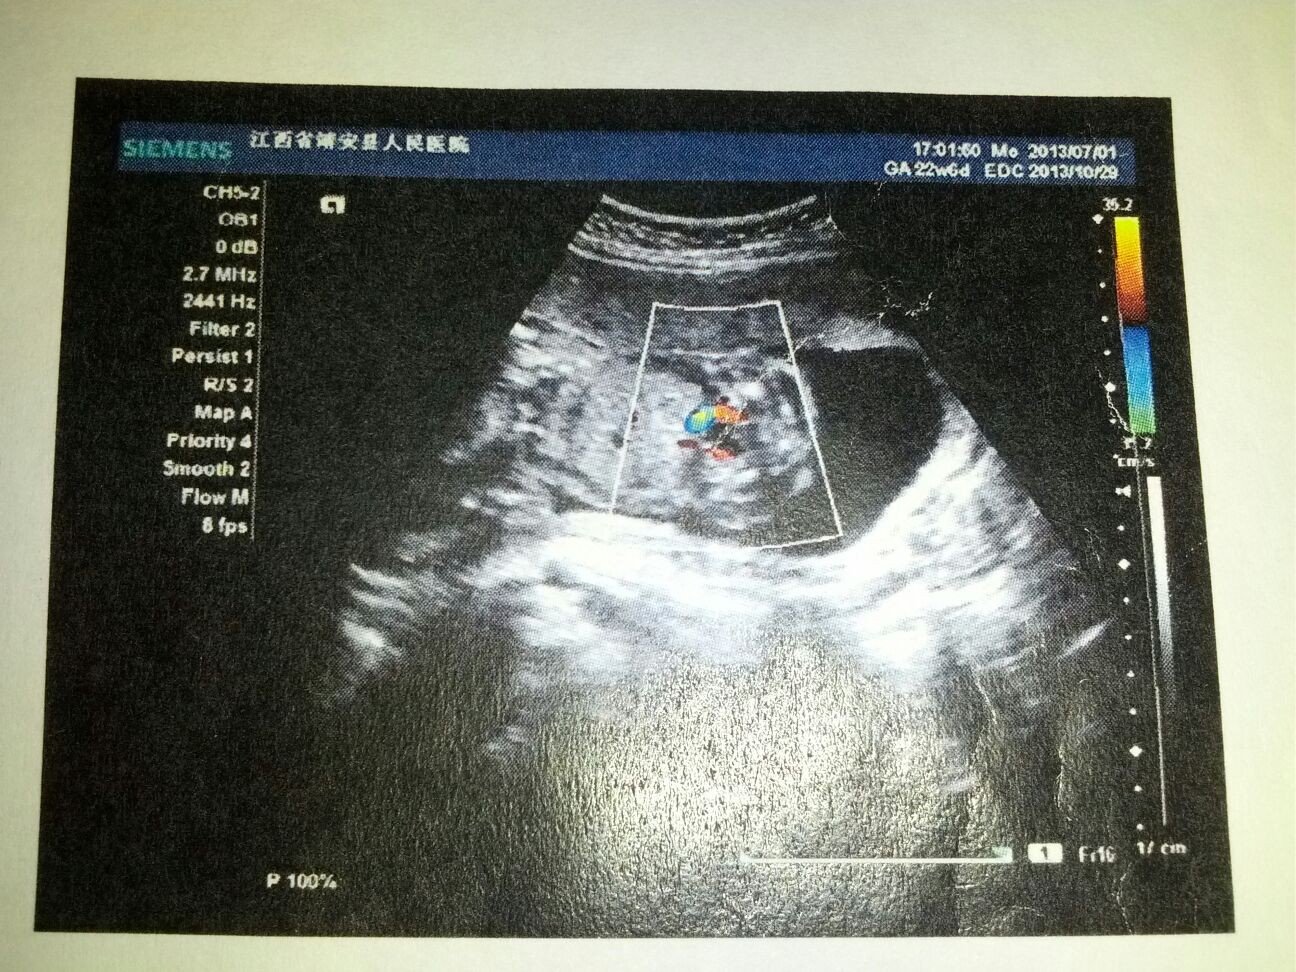

于近侧附件区见一大小约47*36mm的囊实性包块,边界清楚,其内见二个高回声光团,后无声影,大的大小约24*17mm。检查提示:宫内妊娠,单活胎胎盘I度右侧附件囊实性包块,性质待查(囊性畸胎瘤?)

你怀孕几个月了?侧附件区囊性包块是怀孕后内分刺愚泌失调引起的黄体囊肿,一般究菜在怀孕后3个月左右自行消失,不会对宝宝造成影响!囊性畸胎瘤分待查分良性和恶性两种,良性较多做一个病理检查一下!自己不要过于紧张!医生耗稼查应该和你说了吧!!